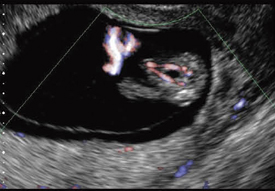

などが考えられる。いずれも胎児病を診断する立場からは重要な事項であるので,この議論は,NTを見たらさらに胎児診断を進めることが結論となる。NTを観察する場合,十分な分解能を持った装置で観察する。特に羊膜とNTとの鑑別が重要となる。できるかぎり羊膜が全周囲に観察できる条件設定が必要である(図2〜4)。

![]() 図2 染色体正常,正常経膣分娩 羊膜とは別にNTが観察される。 この症例は,単一臍帯動脈があり, それによる循環不全がNTの原因と推定された。 |

![]() 図3 単一臍帯動脈 図2と同じ症例。 膀胱の両側に臍帯動脈が観察されるが, この症例では右側1本のみ。妊娠16週。 |